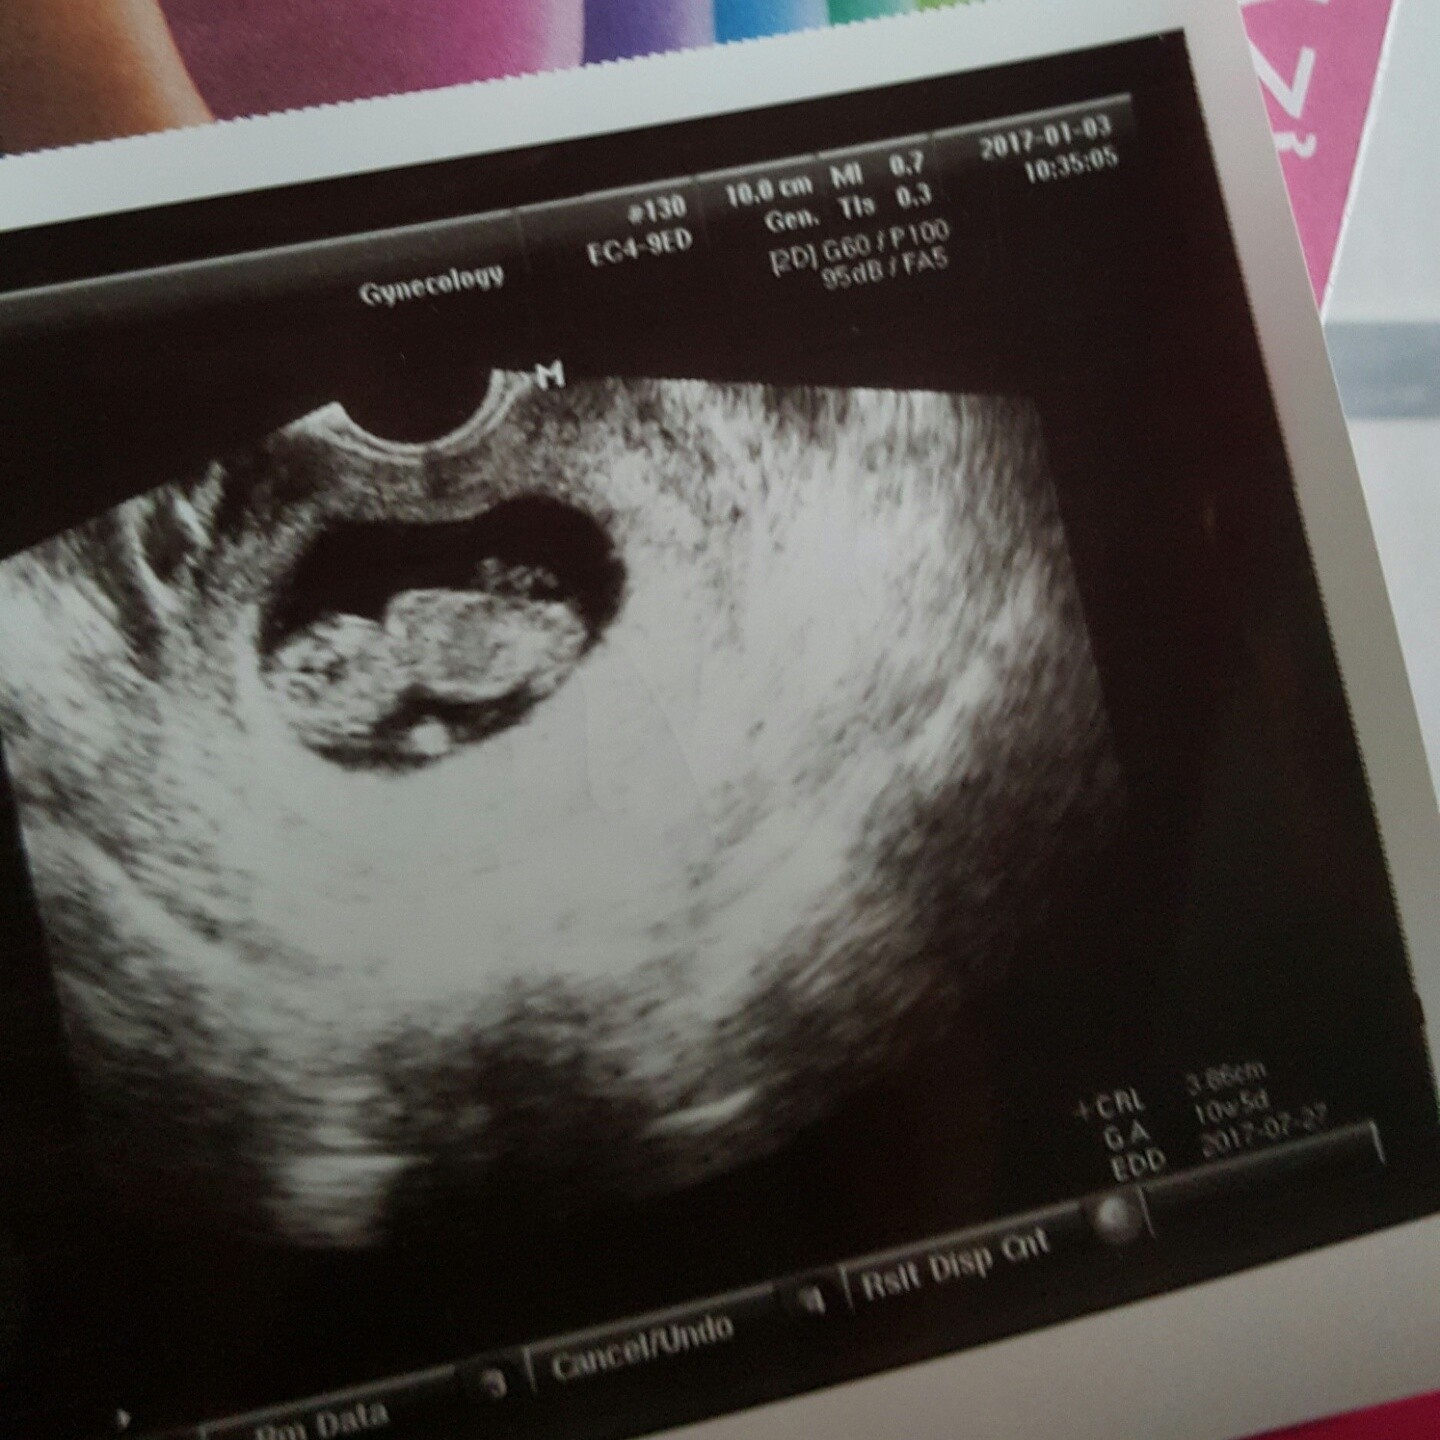

Moja dzisiejsza fasolka :-)

Z usg dziś termin wyszedł na 27.07 a nie 1.08